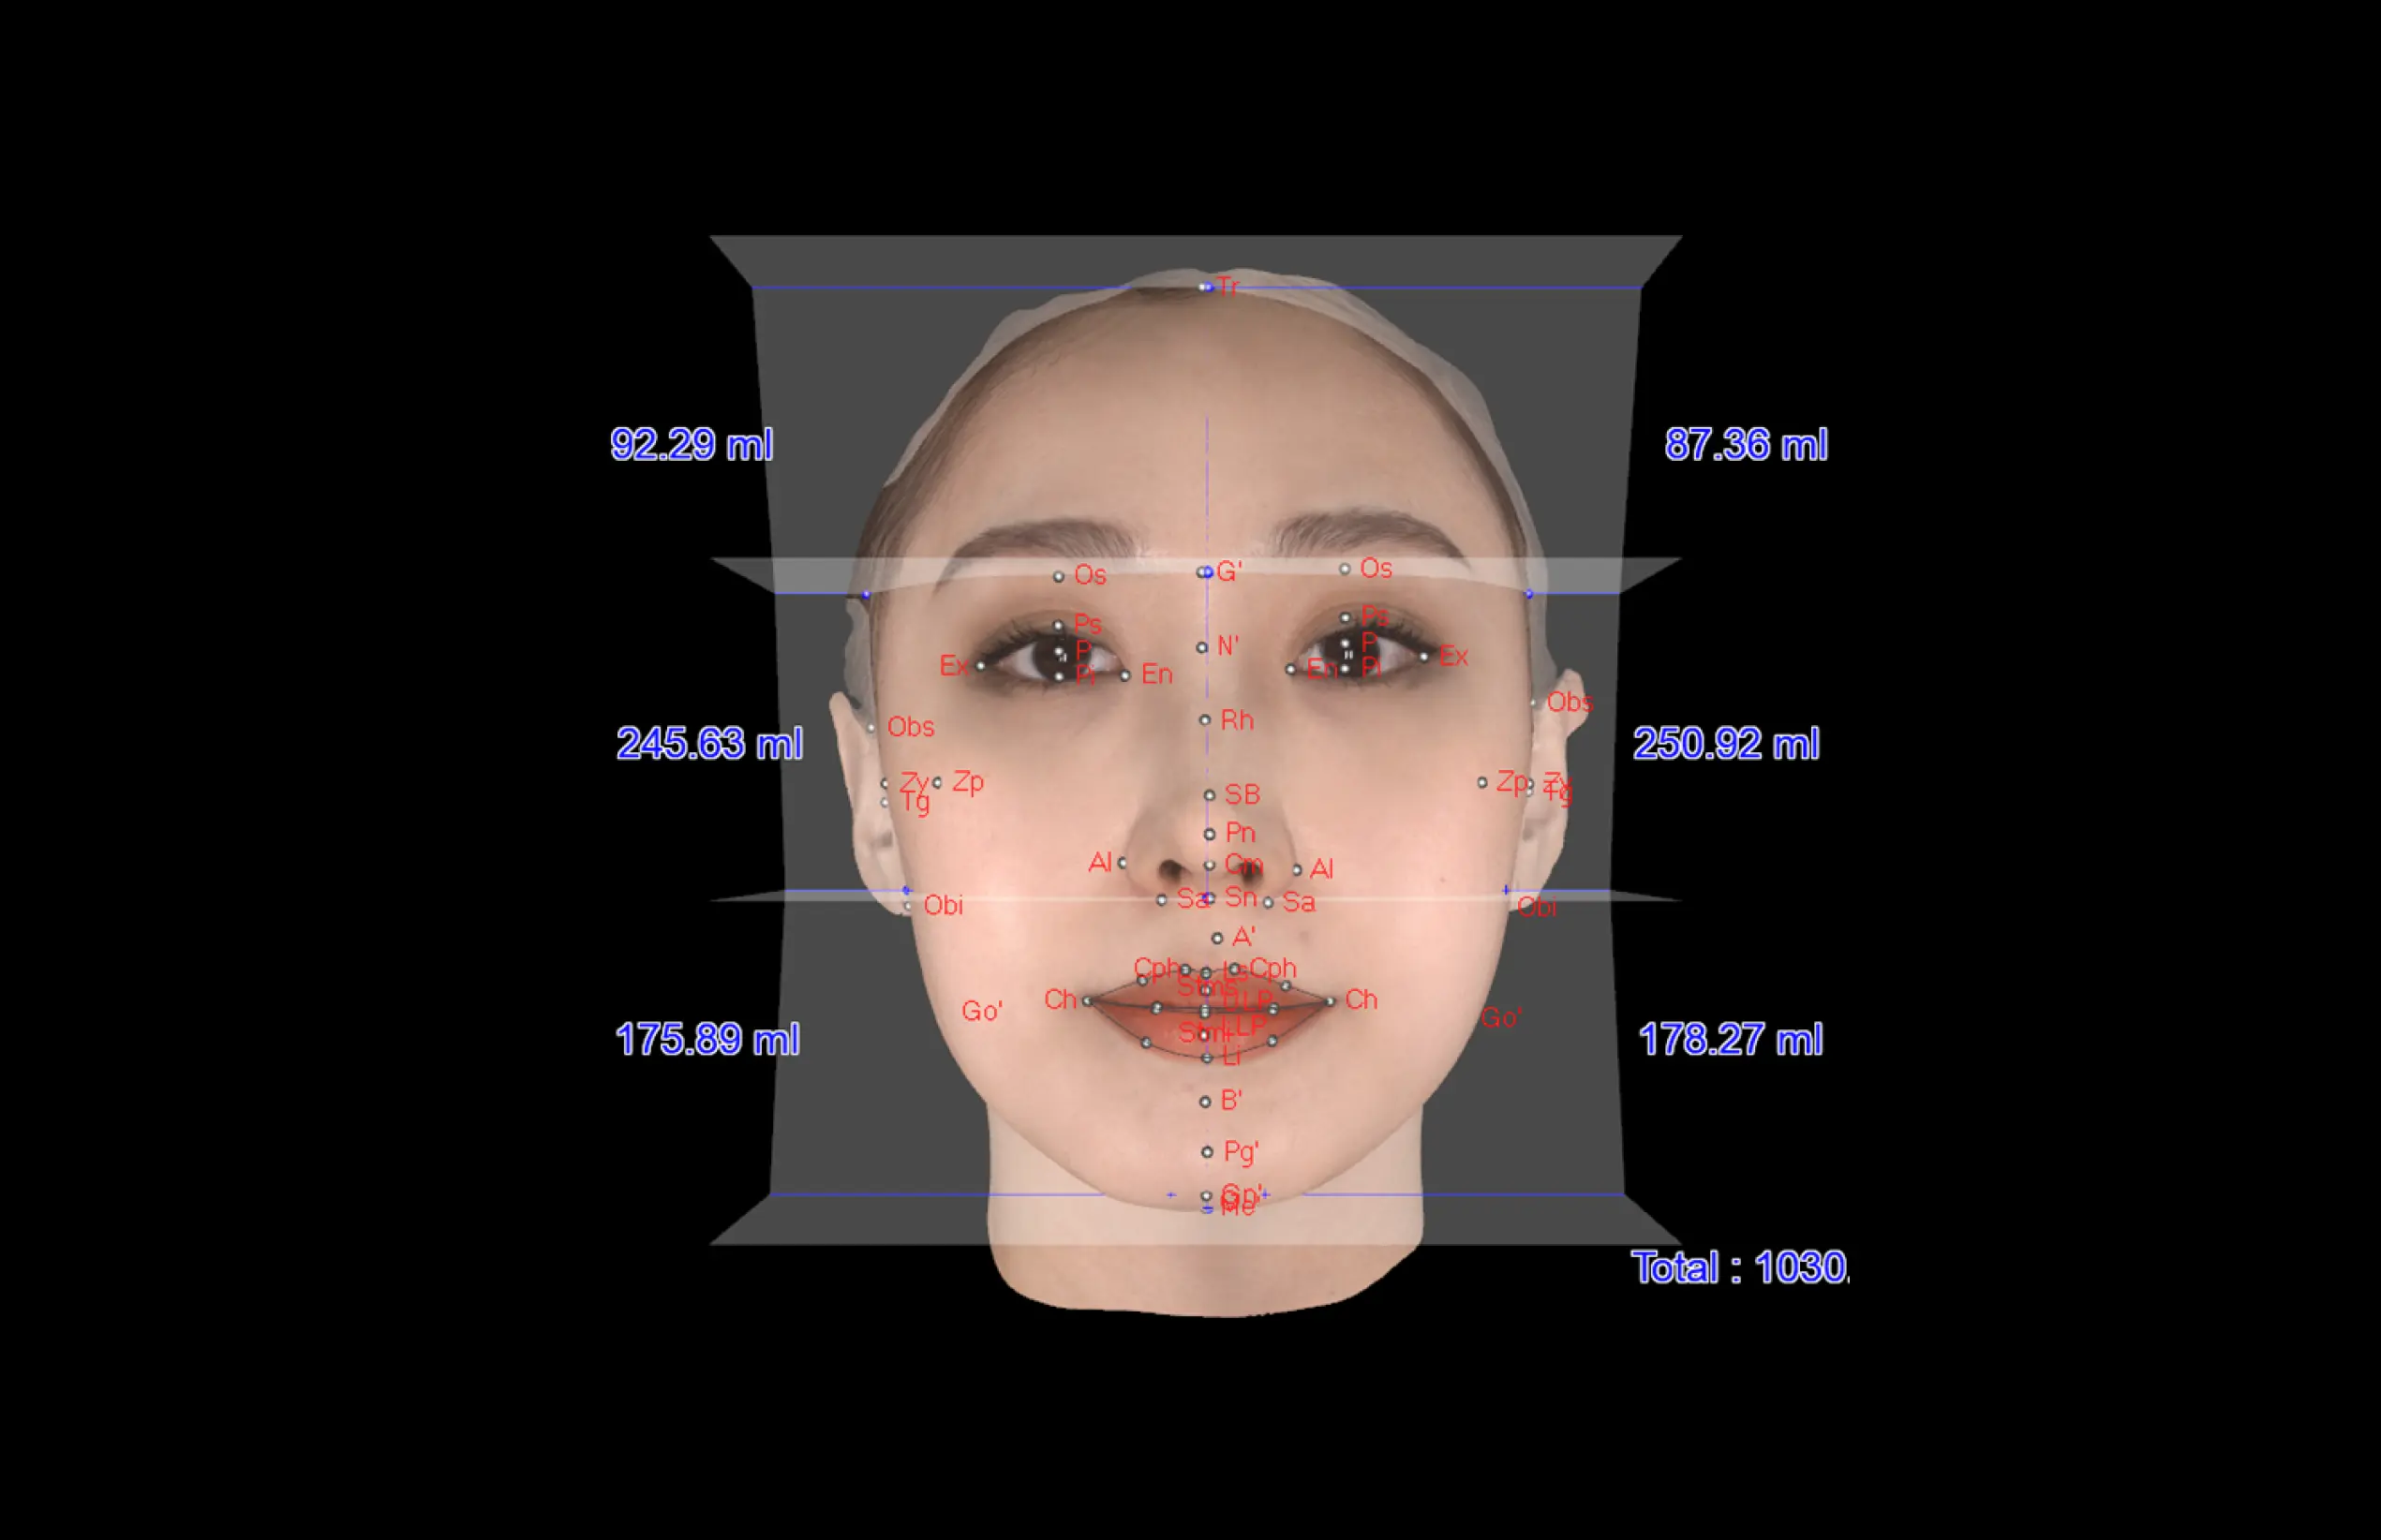

더보기 눈과 미간의 균형

·얼굴 상안, 중안, 하안의 직선 너비

·안각간 거리와 좌·우안 거리의 비율을 측정

하는 수평적 분석